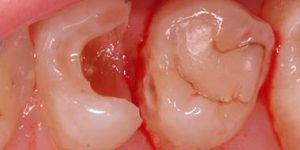

Работы наших специалистов по лечению каналов зуба